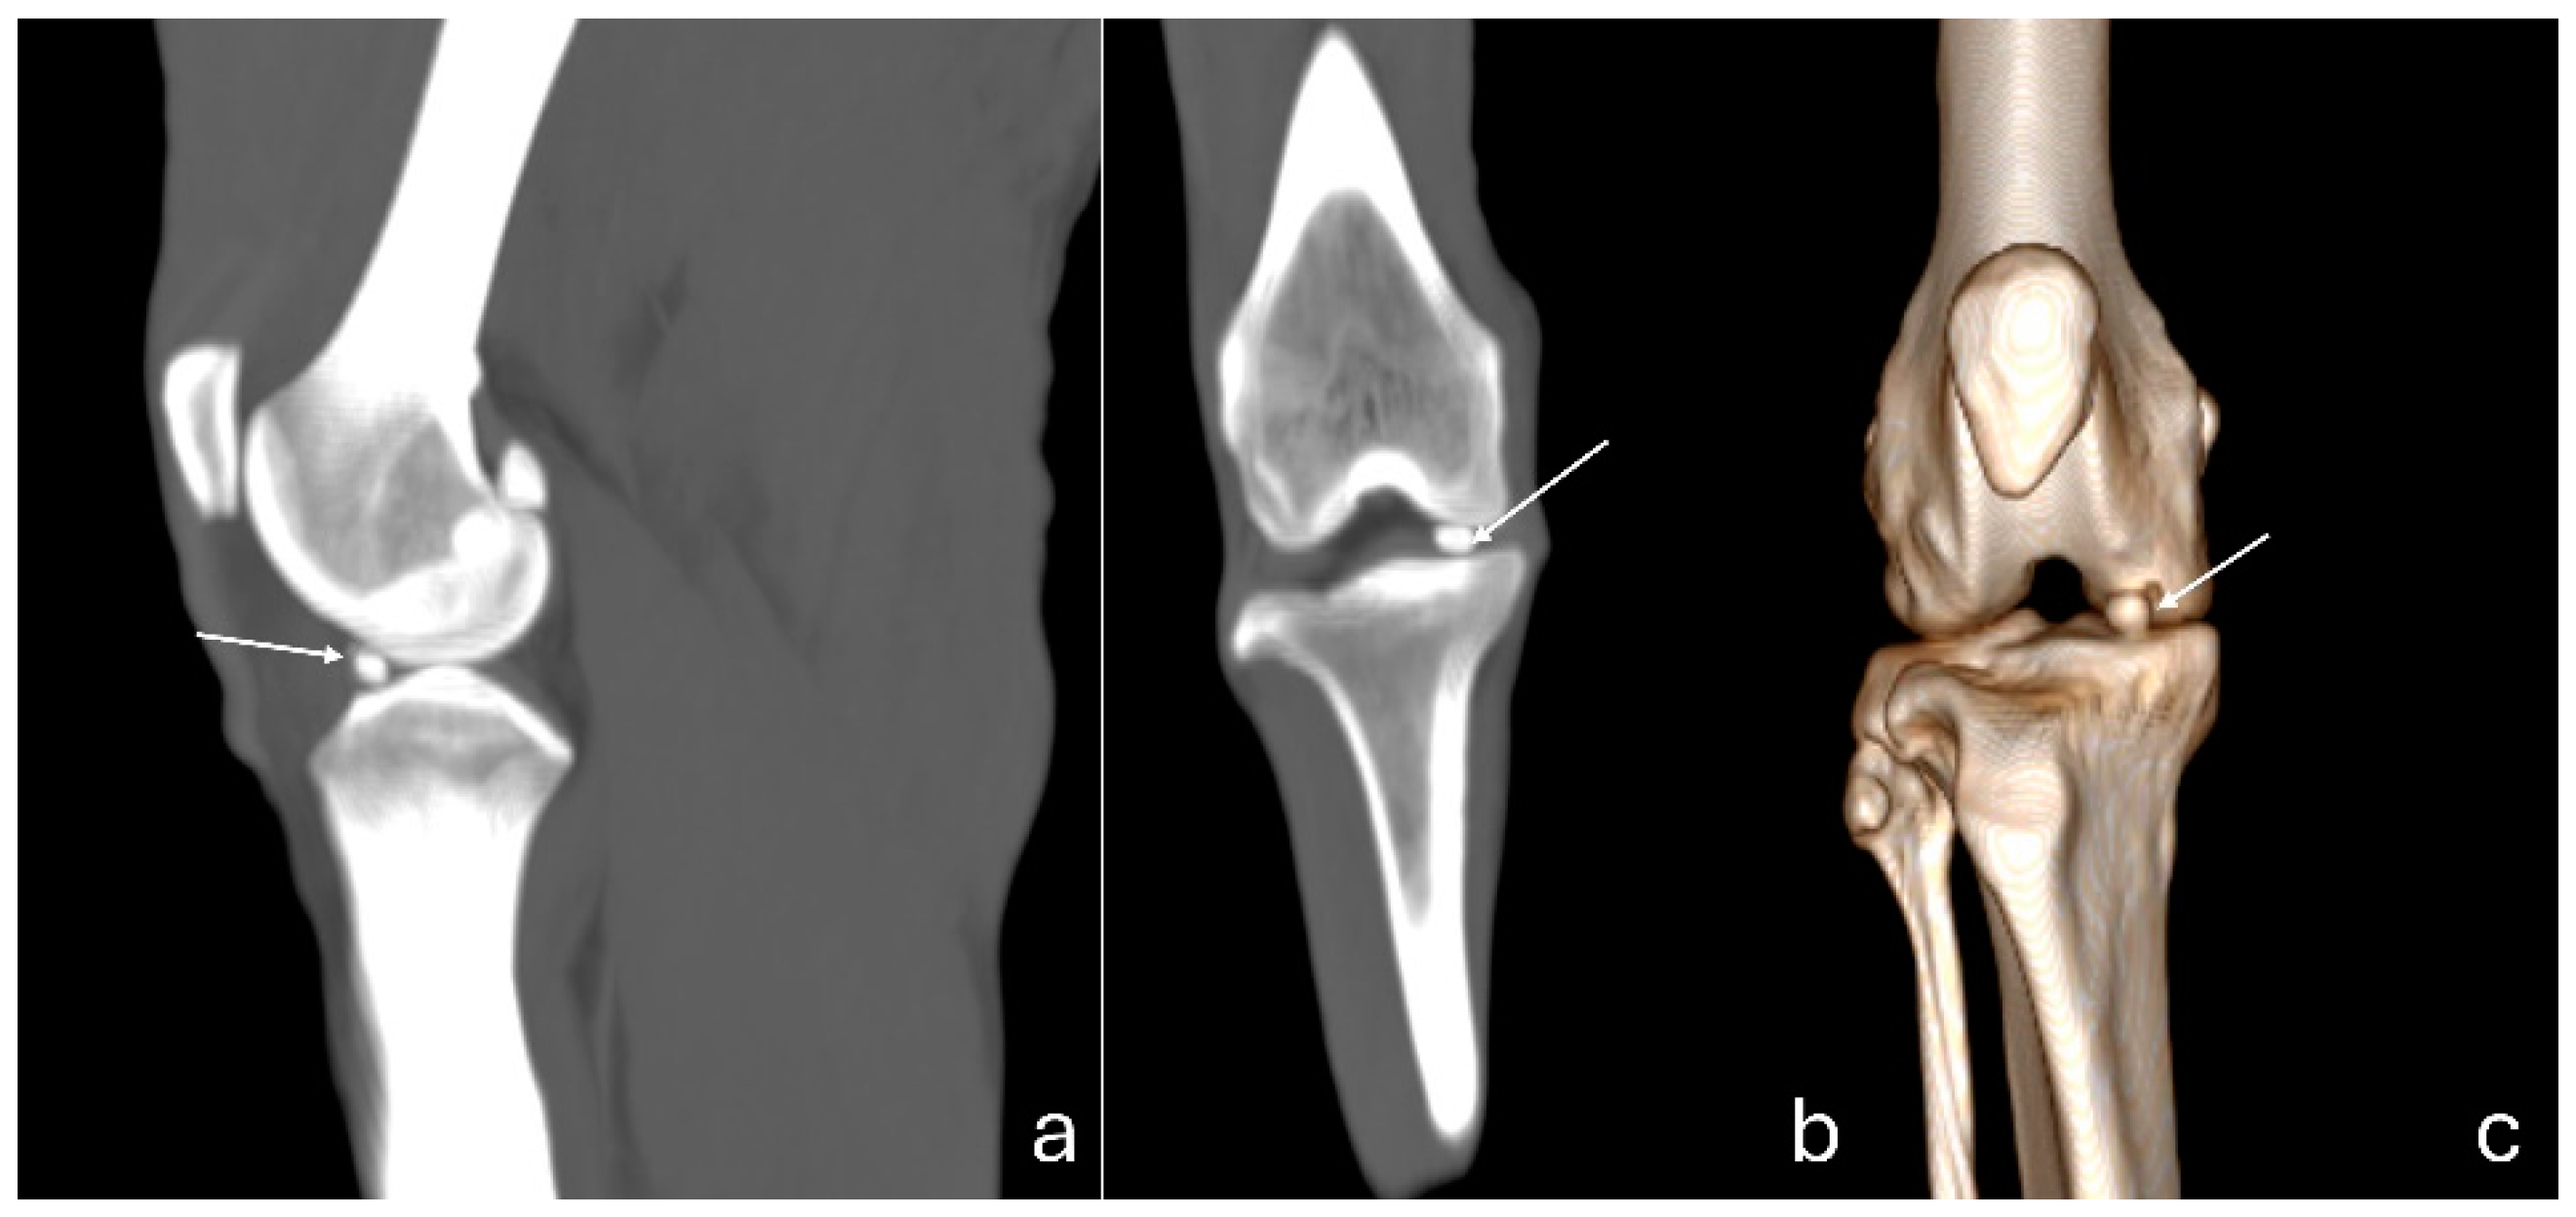

Figure 4. Computed tomography images of an adult puma stifle joint (Puma concolor). Sagittal (a) and dorsal planes (b), and a cranial view of the 3D reconstruction (c). Observe mineralization of the medial meniscus (arrow).

The 3D reconstruction of CT images (Figure 2c) revealed, in a cranial view, the patella as a raindrop-shaped structure with a wider base than the apex, positioned in the symmetrical trochlear groove. Meniscal mineralization was identified in the stifles of the same four animals as a hyperdense portion in the medial compartment. The caudal and lateral views displayed the lateral and medial fabellae in the epicondylar region of the lateral and medial condyles, respectively, with the lateral one being larger (Figure 2d). Other bone structures showed similar patterns as seen in radiographic images. Multiplanar and cross-sectional images allowed identification of the patella, infrapatellar fat, cranial cruciate ligament (from the caudal portion of the femur to the cranial area of the tibia), caudal cruciate ligament (from the cranial aspect of the femur to the popliteal margin of the tibia) and meniscofemoral ligament (Figure 3). The menisci were more difficult to identify, but those with partial mineralization were easily visualized (Figure 4). The fabellae and sesamoid of the popliteal were also identified; all had a thin cortical layer.

In the stifle joints where meniscal mineralization was identified, it was recognized in all imaging modalities in the medial meniscus. A CT scan of Panthera tigris described the meniscal mineralization as dense cortical bone surrounding a less dense stroma, similar to the structure of the patella and fabella [10]. In the present study, the meniscal mineralization exhibited a HU range of 924-931, lower than cortical bone (HU range of 1159.375-1363.5) and higher than trabecular bone (HU range of 373.875-632.12) found in various sesamoids.